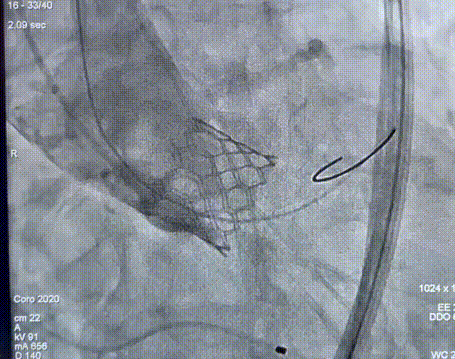

快速起搏下瓣膜释放

瓣膜释放

复查造影示无PVL,形态良好,超声提示流速1.5m/s

瓣膜释放后造影